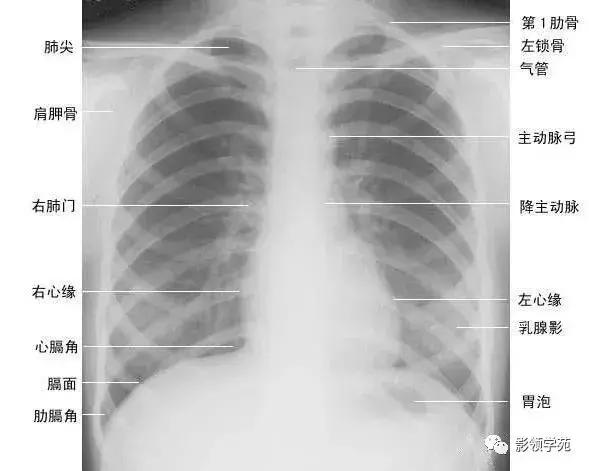

正常胸廓由软组织与骨骼组成,两侧对称(如下图)。

1、胸锁乳突肌及锁骨上皮肤皱褶 胸锁乳突肌起自胸骨柄及锁骨内端,向后上方斜行,止于乳突,在两肺尖内侧形成外缘锐利且较均匀的致密阴影。在胸骨头和锁骨头及锁骨之间形成一个小三角间隙,叫锁骨上窝或胸锁乳突肌间隙。当颈部偏斜时,两侧胸锁乳乳突肌阴影可不对称,勿误为肺尖部病变。锁骨上皮肤皱褶为与锁骨上缘平行的薄层软组织影,其厚度为3~5mm,内侧与胸锁乳突肌阴影相连,略成直角,系锁骨上皮肤及皮下组织的投影。

2、胸大肌起于锁骨的外侧分,胸骨和第1~6肋软骨,肌束行向外上方,至于肱骨大结节嵴。在肌肉发达的男性,于两肺中部的外侧形成扇形均匀致密影,下缘锐利呈斜行曲线,自肺野伸向腋部,与腋前皮肤皱褶相延续。

3、乳房及乳头 女性乳房于两下肺野形成半圆形的密度增高影,其下缘清楚,并向外与腋部皮肤连续,上缘不清,且密度自下而上逐渐变淡以至消失,其位置随年龄的增长而下垂,一般两侧对称。乳头在两下肺野相当于第5前肋间处形成边缘清楚的小圆形致密阴影,乳房越薄,乳头影境界越清晰,其特点亦为左右对称。青春期乳头呈半球状,约在第2~6肋之间。妊娠期乳腺可明显增大,至哺乳期结束后,乳房逐渐缩小,失去弹性而下垂,到老年期,乳房逐渐萎缩。

胸廓前有胸骨、锁骨,后有胸椎、肩胛骨,肋骨则围绕其间。

1、肋骨共12对,每根肋骨分为前肋、腋段和后肋三段:同一肋骨前后段的位置不同,一般第6前肋与第10后肋等高。前段扁薄,密度略低,自外上向内下倾斜走行并形成肋弓;后段圆厚,密度略高。呈水平状向外下走行;在无变异的情况下,两侧肋骨的位置及肋间隙的宽度基本对称,故肋骨及肋间隙常被用作胸部病变的定位标志。第1~10肋骨前端有肋软骨与胸骨连接,因肋软骨未钙化时不显影,故肋骨前端多呈游离状。25岁以后第1对肋软骨首先钙化,其他肋软骨随年龄增长,自下而上逐条钙化。第一肋骨常常显示不规则钙化区,尤其是中年以后。下部诸类也显示局限性的钙化,即使在成年人也是这样。在女性的软骨钙化常常示不规则的,造成斑点状形态。而在男性钙化可以局限于软骨之上下缘,造成线样阴影。有时下肋部肋软骨的钙化极为广泛,造成下肺野内带不规则的斑点状致密影。肋骨有很多种先天变异(下图),常见的有以下几种:

在常规前位x胸片上,肋骨特别是其后部非常分明,第一肋骨的前端宽大恰好位于锁骨水平之下,由此可以识别,也可以借助和他构成关节的第一胸椎至关系来识别。第一胸椎和第七颈椎的鉴别可由他们的横突方向来判断,前者横突下上,向外倾斜,而后者横突指向下外方。这种鉴别对于有颈肋者颇有价值,因为有时颈肋很长与第一肋骨极为相似。

2、肩胛骨在标准后前位胸片上,应投影于肺野之外,如两肩向前旋转不够或于前后位,尤其是卧位投照时,胛骨影可呈带状重叠于中上肺野的外侧部。

3、锁骨 在标准后前位胸片上,两侧锁骨内端亏蝇骨柄形成胸锁关节,该关节到中线的距离应相等:两侧锁骨外端与肩峰形成肩锁关节。

4、胸骨 在标准后前位胸片上,大部分胸骨与纵隔阴影重叠,仅胸骨柄两侧外上缘可突出于纵隔影之外,投照位置略有偏斜时尤为常见,其在侧位和斜位片上可全貌显示。

5、胸椎在标准后前位胸片上,胸椎位于纵隔阴影内,透过气管影可清晰显示第1~4胸椎,而心脏后方的胸椎仅隐约可见。